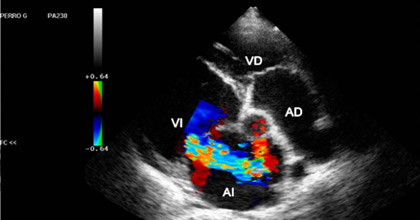

Estudio de imagen no invasivo que mediante el uso de ultrasonido permite representar la estructura del corazón y analizar el flujo de la sangre a través de sus cavidades.

• Análisis de la anatomía y funcionamiento de las válvulas cardíacas.